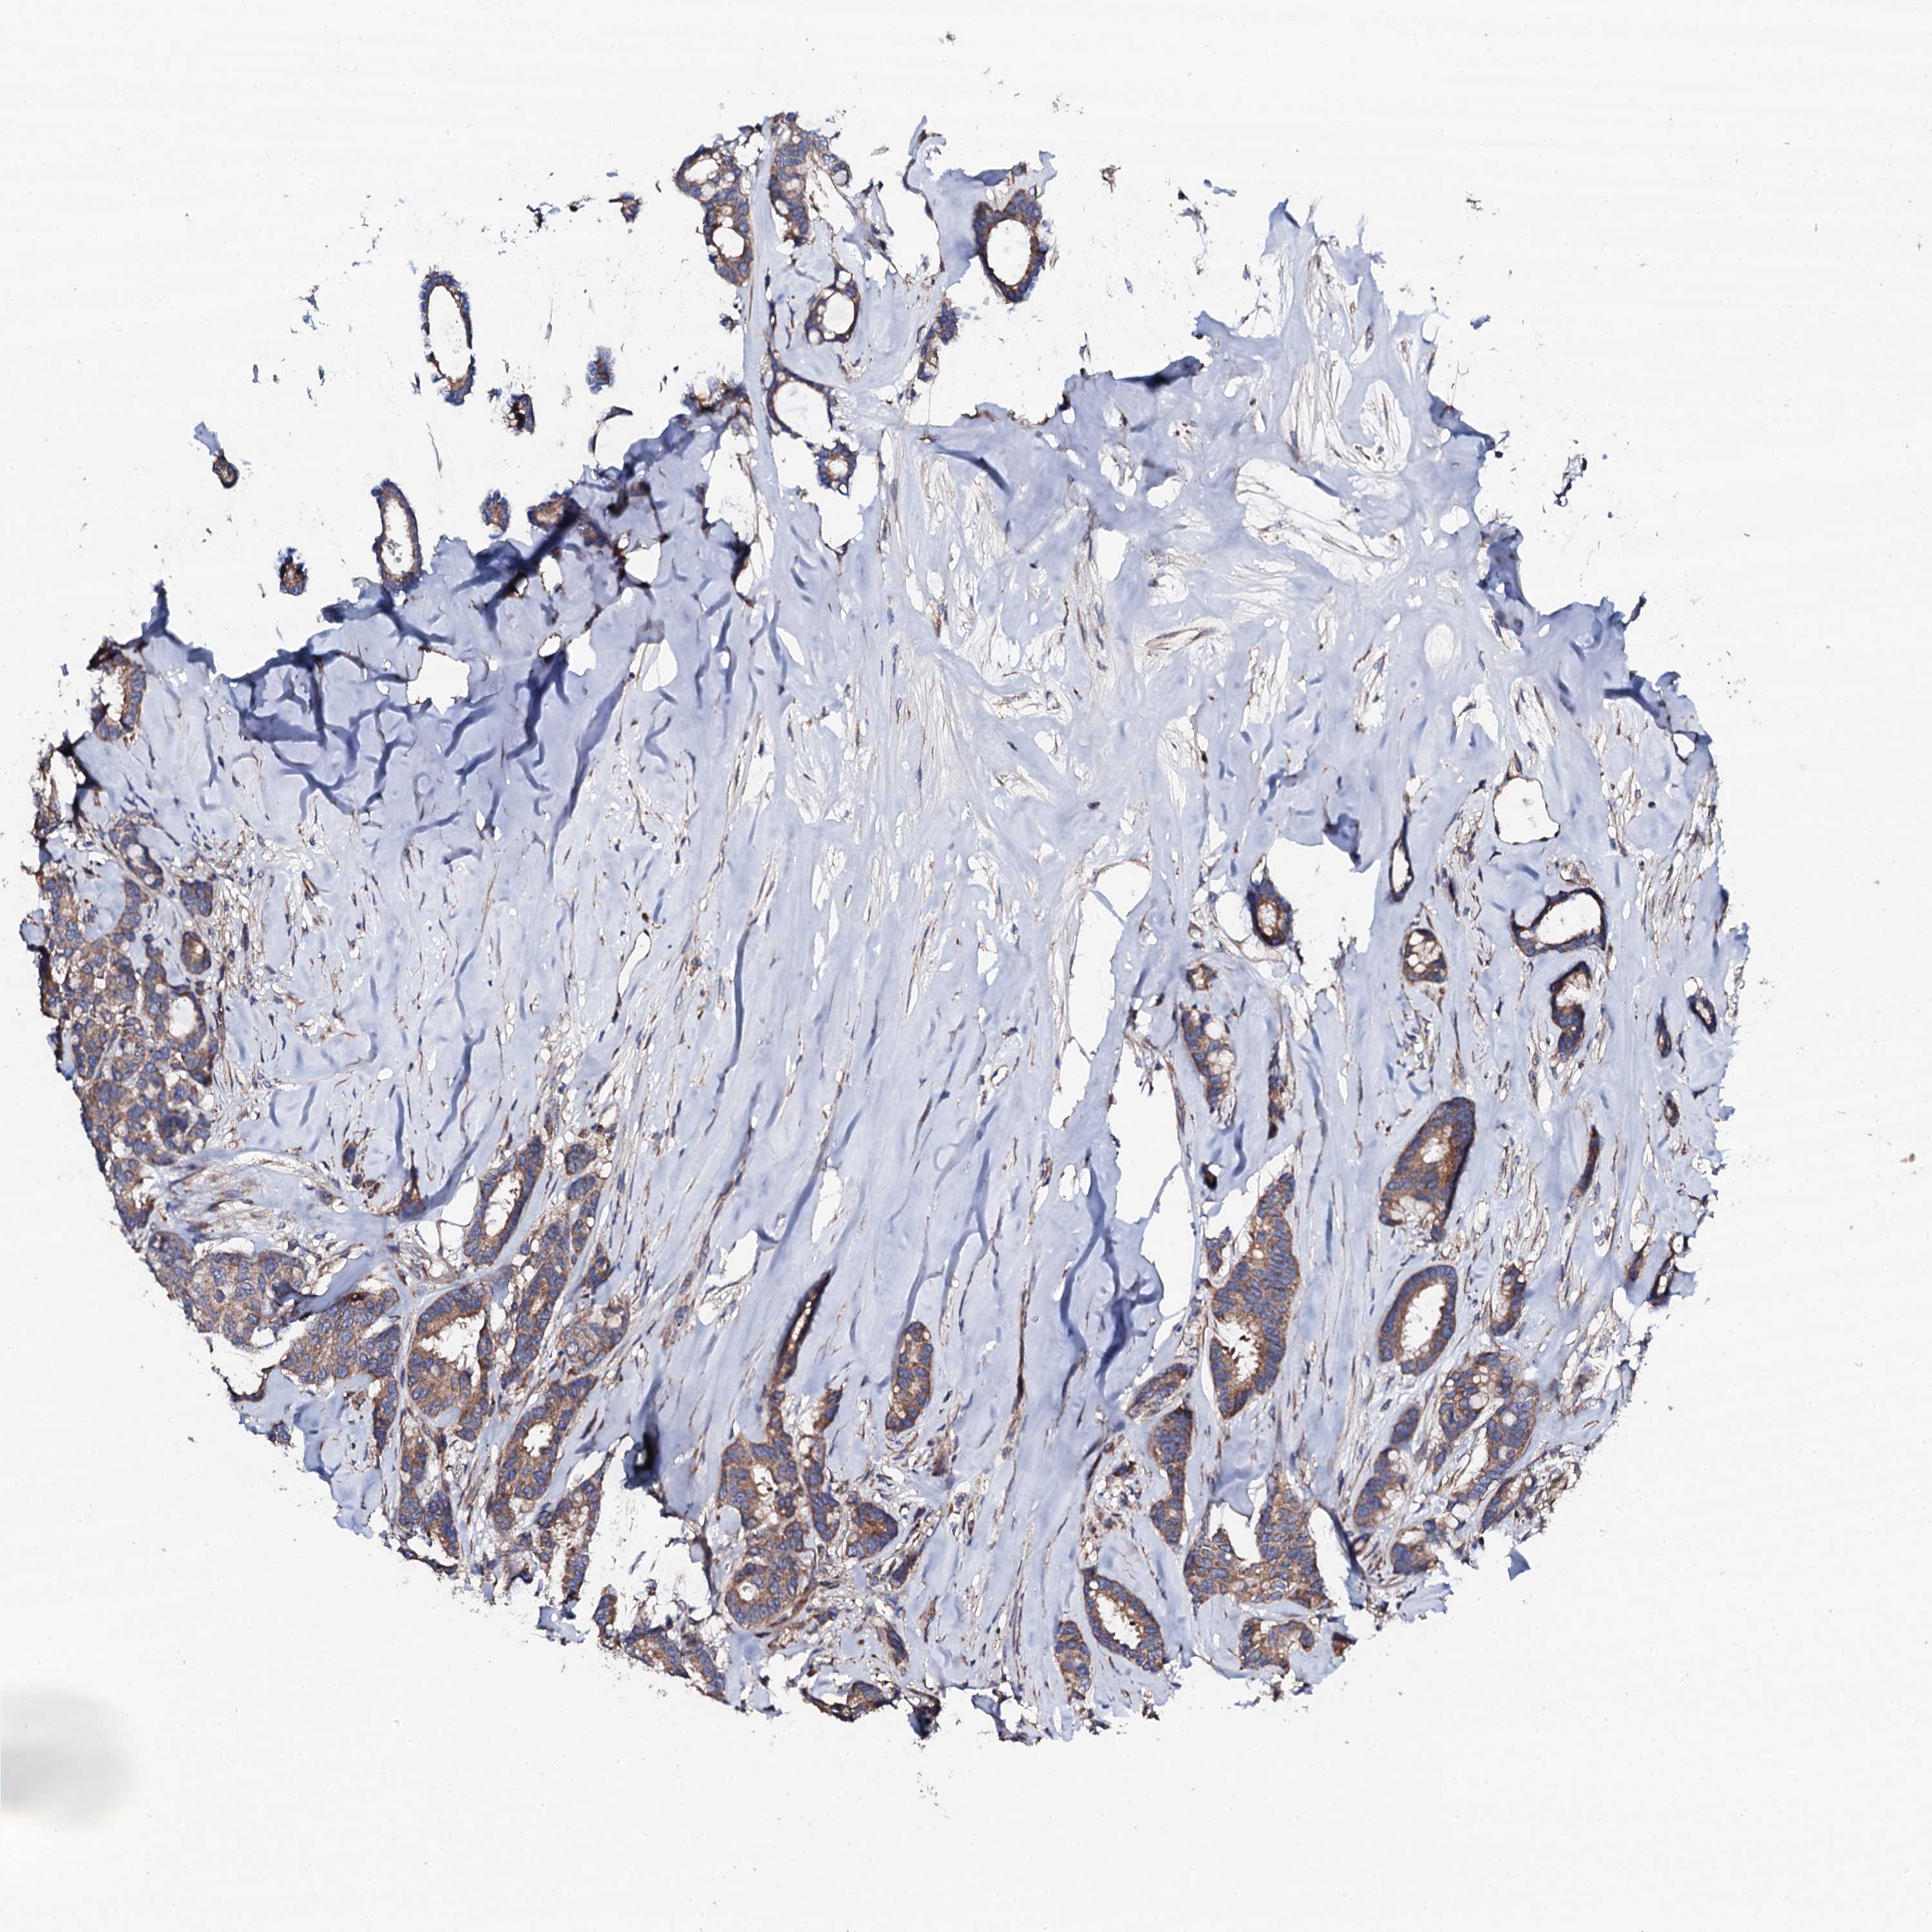

CANCER BREAST CANCER Show tissue menu

BRCA TCGA BRCA VALIDATION PROTEIN EXPRESSION

ANTIBODIES

AND

VALIDATION